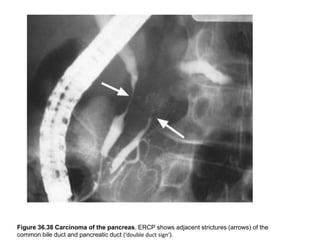

Figure 36.38 Carcinoma of the pancreas. ERCP shows adjacent strictures (arrows) of the

common bile duct and pancreatic duct (‘double duct sign’).

Figure 36.38 Carcinomaof the pancreas. ERCP shows adjacent strictures (arrows) of the common bile duct and pancreatic duct (‘double duct sign’).